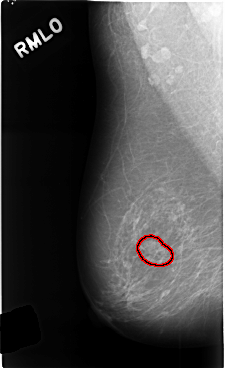

C_0454_1.RIGHT_MLO

FILE: C_0454_1.RIGHT_MLO.OVERLAY

TOTAL_ABNORMALITIES 1

ABNORMALITY 1

LESION_TYPE MASS SHAPE LOBULATED MARGINS CIRCUMSCRIBED

ASSESSMENT 3

SUBTLETY 4

PATHOLOGY BENIGN_WITHOUT_CALLBACK

TOTAL_OUTLINES 1

BOUNDARY